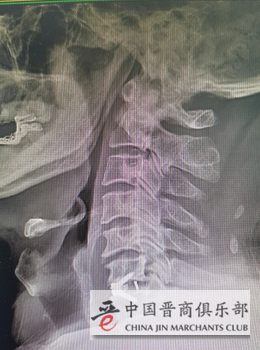

患者术后影像

韦向荣主任介绍,长期以来,以前做颈椎间盘突出症的手术使用的是钛板为主要术式,但部分患者由于钛板放在椎体前方可出现咽部不适、吞咽困难等并发症。颈椎前路零切迹椎间融合器的使用,具有对颈椎及椎前结构干扰和破坏小、手术创伤小、出血少等优点,有效降低了术后患者吞咽困难及邻近节段退变的发生,从而降低术后并发症,提高临床疗效。